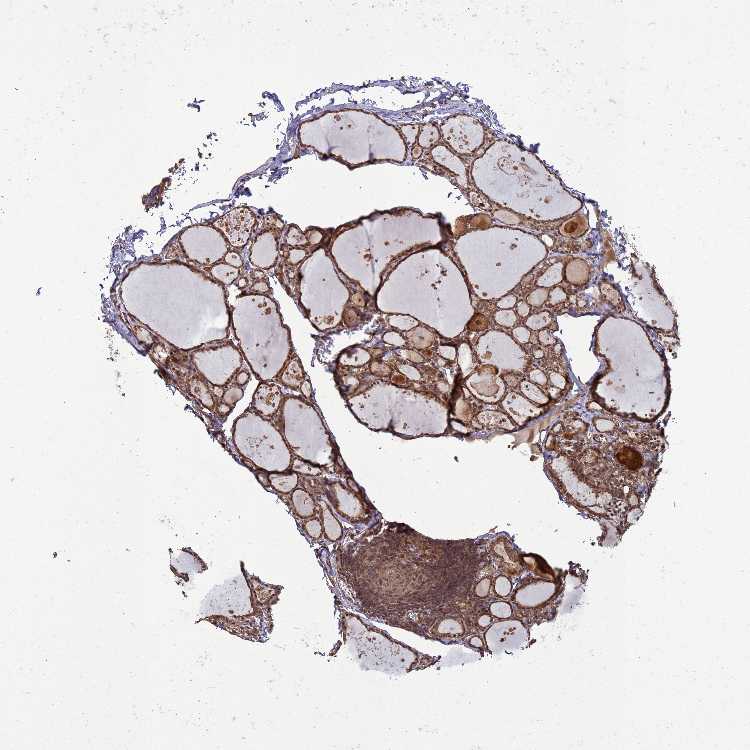

Antibody HPA045910

Glandular cells High